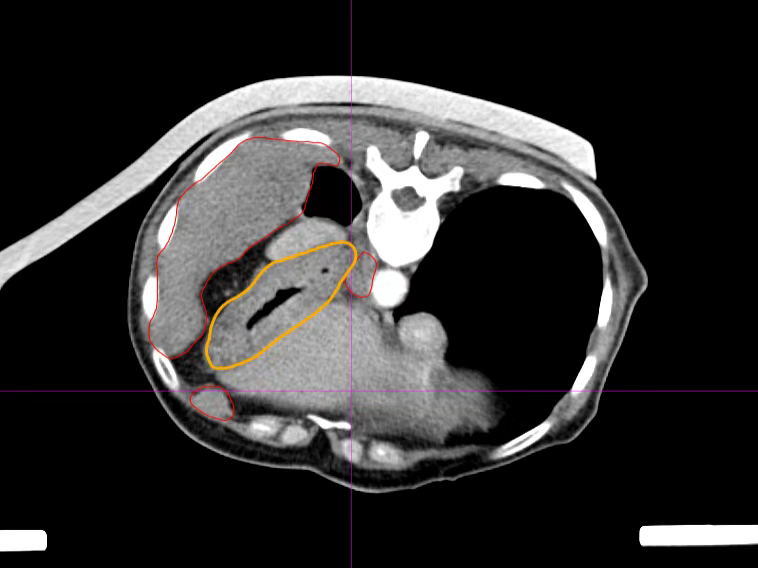

The relationship between the lesion and the stomach before placing the gauze pad (red indicates the lesion, yellow indicates the stomach)